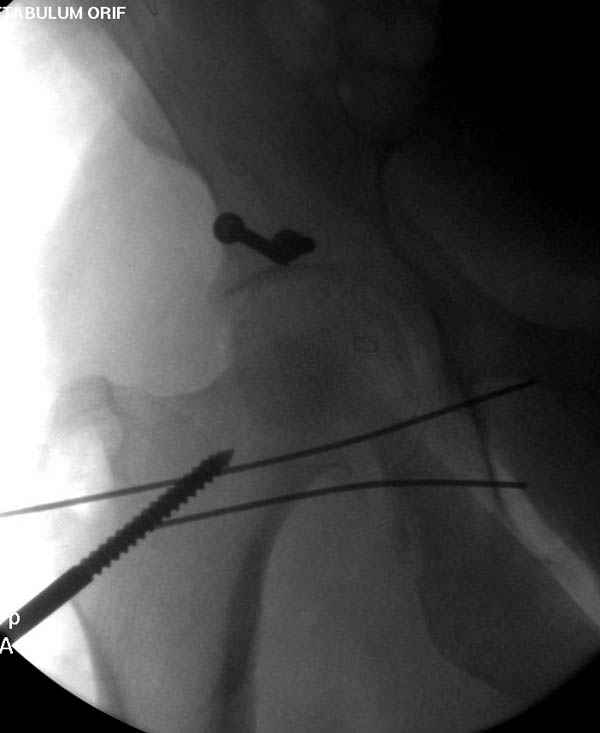

Наш недавний случай перкутанной фиксации "методом

Сиэтла" спицами 2.8 мм с резьбой на конце.

Дополнительно имеется перелом ацетабулума: задняя

колонна с полупоперечным переломом, и переломы костей лица.

На седьмой день зафиксирован перелом ацетабулума через задний доступ. Перед операцией для профилактики DVT, IVC фильтер, также получает Lovenox.

Извиняюсь за качества снимков, обычный больной в 300 фунтов, портативным ренген аппаратом не пробить.